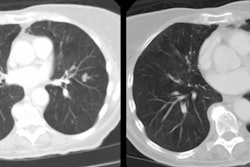

The patient shown in the case below was referred for evaluation of a right upper lobe mass. The CT scan demonstrates a large mass in the right upper lobe that contained macroscopic fat consistent with a hamartoma. Lung windows demonstrated the lesion to be endobronchial and this was confirmed at surgical resection. (Click images to enlarge)